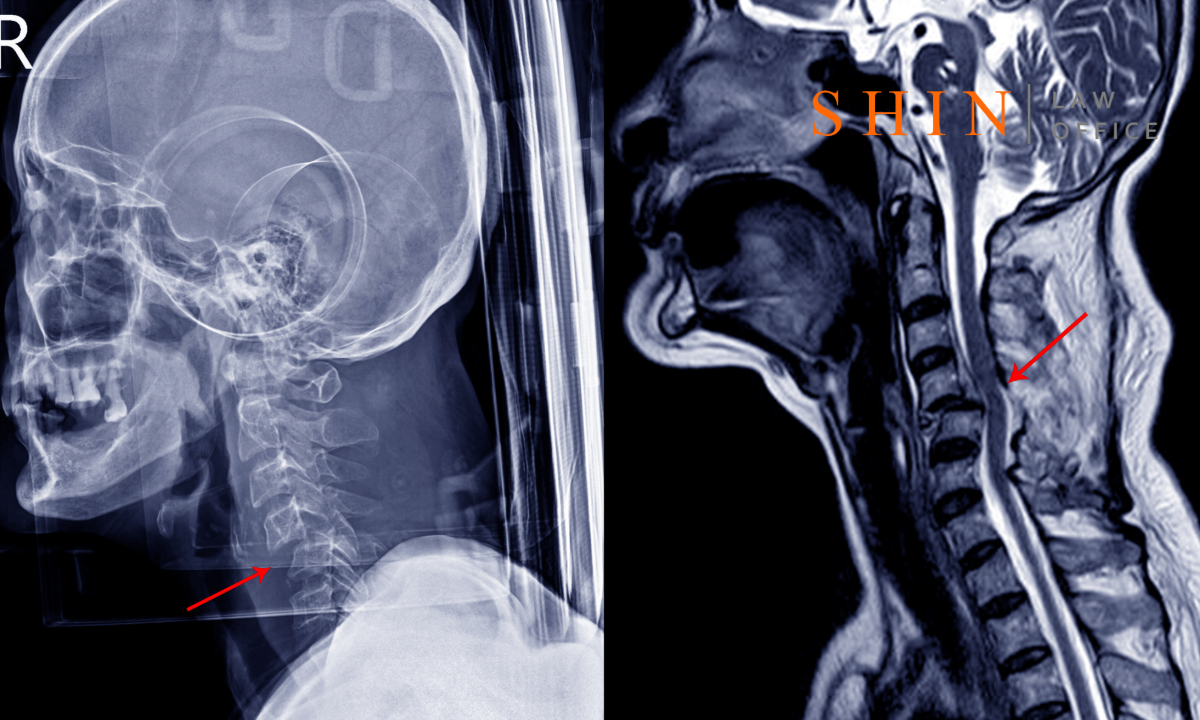

Neck injuries range from mild soft-tissue sprains to severe spine trauma. In many cases, the injury is “invisible” – no bone breaks, no cuts – yet the pain and muscle spasms are real. Common symptoms include neck pain, limited range of motion, shoulder or upper back pain, dizziness, headaches, or numbness in the arms. For example, an injured person often reports that “something pulled in the back of my neck” at impact. Doctors take these complaints seriously and may order X-rays or an MRI to rule out fractures or disc herniations. They often diagnose muscle or ligament strains and prescribe therapy.

3. Medical Evidence: Your medical records are the backbone of your claim. Virginia law does not require a certain injury threshold – even a soft-tissue “sprain” can warrant damages – but you must show the injury. If there are positive findings (e.g. muscle spasms, ligament strain, disc bulge), highlight those. For instance, in Foster v. McNamara (2025), the plaintiff had ligamentous instability in his neck on X-ray. This gave objective proof of injury that he could relate to the crash (with proper expert interpretation).

4. Expert Testimony: To connect the dots between the crash and your injury, Virginia trials often involve expert witnesses. Traditionally, that meant medical doctors. A new Virginia law now allows chiropractors, too. Under Va. Code § 54.1-2900, chiropractors are authorized to treat spine and joint injuries. And Va. Code § 8.01-401.2(A) authorizes non-doctors to testify on medical causation for injuries within their scope. In Foster, the Court of Appeals held that barring a chiropractor from testifying on the cause of neck injuries was error. Simply put, if you are treated by a chiropractor who uses X-rays or MRI reports, that expert can testify on how the crash caused your neck injury.

Practically, you or your lawyer should identify treating physicians or chiropractors who can testify. For example, if your MRI shows a bulging disc, a neurosurgeon or orthopedist can explain how that condition relates to the trauma. If you saw a chiropractor soon after the accident (within weeks), that chiropractor can credibly say your neck sprain stemmed from the collision. Be aware: Defense lawyers will look for anything to undercut your experts, so make sure all your evidence – records, notes, bills – is consistent.